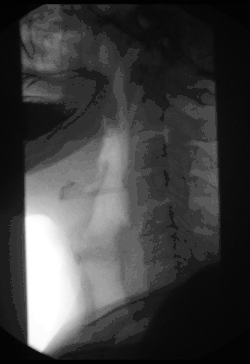

Esofagograma

El esofagograma, también denominado trago de bario, es un estudio de gabinete, que consiste tomar radiografías en varias posiciones para obtener imágenes del esófago, con el fin de determinar alteraciones de la anatomía normal, para lo que el paciente ingiere un medio de contraste opaco a los rayos X (generalmente sulfato de bario diluido en agua, en caso de sospecha de ruptura del tracto se utiliza contraste iodado).